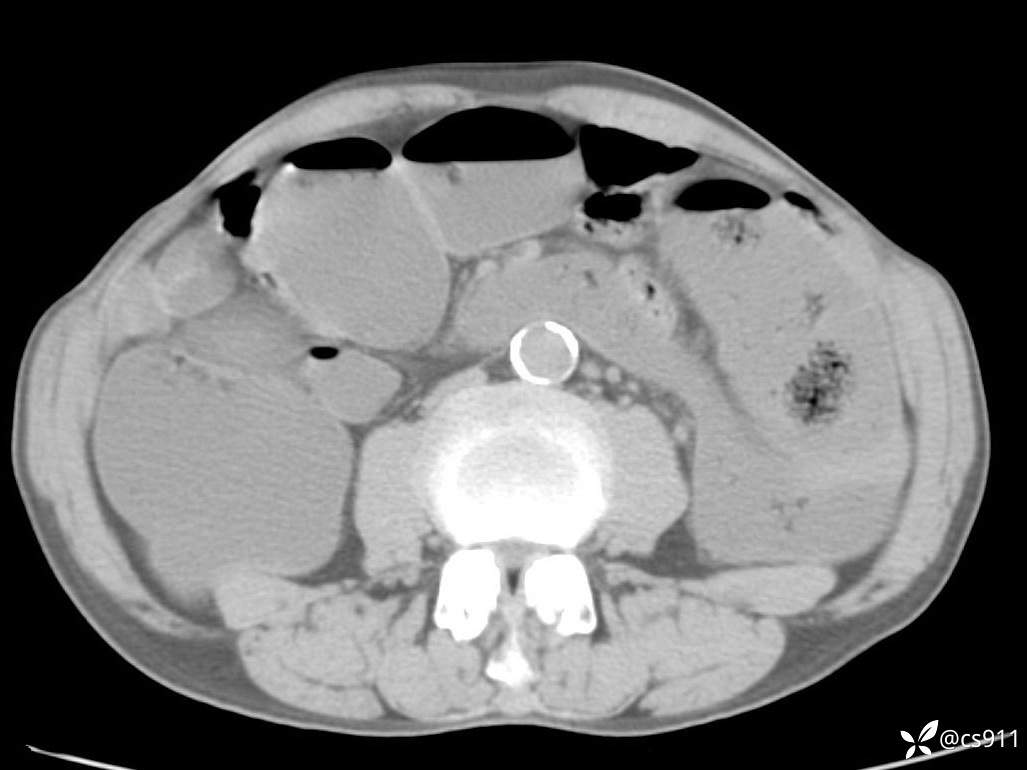

急腹症之急诊CT,原因?答案公布

男,77岁,腹痛、腹胀伴恶心呕吐1天。呕吐胃内容物,非喷射性呕吐,有咖啡色样胃内容物,诉有胃穿孔病史。查体:全腹平,下腹部压痛,全腹无反跳痛,叩诊呈浊音,移动性浊音阴性,肠鸣音减弱,1-2次/分。肛检:直肠未扪及明显肿物,可触及大量粪块。

T 36.6℃ P 80次/分 R 26次/分 BP 100/60mmHg

白细胞(WBC) H 14.55 10e9/L 4-10

中性粒细胞百分率(NEUT%) H 85.7 % 40-75

血淀粉酶(AMY) HH 1859 U/L 35-135

癌胚抗原(CEA) H 27.44 ng/ml 0-5

呕吐物 潜血试验 * 阳性 阴性

患者轮椅入室检查神志清楚, 能配合摆位和呼吸